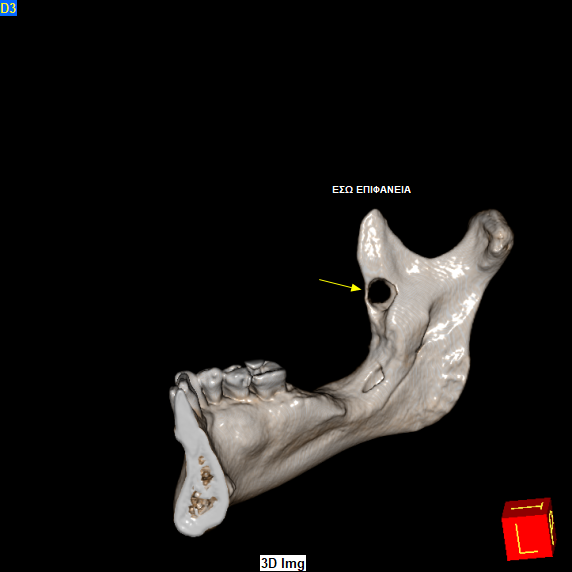

Τον Φεβρουάριο του 2024 ο ασθενής παραπέμφθηκε για CBCT άνω και κάτω γνάθου προκειμένου να προχωρήσει σε οδοντιατρικές εργασίες. Στο CBCT παρατηρήθηκε η παρουσία μικρού μεγέθους υπόπυκνης αλλοίωσης στο πρόσθιο χείλος του δεξιού κλάδου της κάτω γνάθου η οποία είχε προκαλέσει λύση των συμπαγών πετάλων.

Όπως αποδείχθηκε επρόκειτο για Αδαμαντινοβλάστωμα, και συνεπώς υποτροπή της αρχικής βλάβης που πρωτοεμφανίστηκε προ 3ετίας!